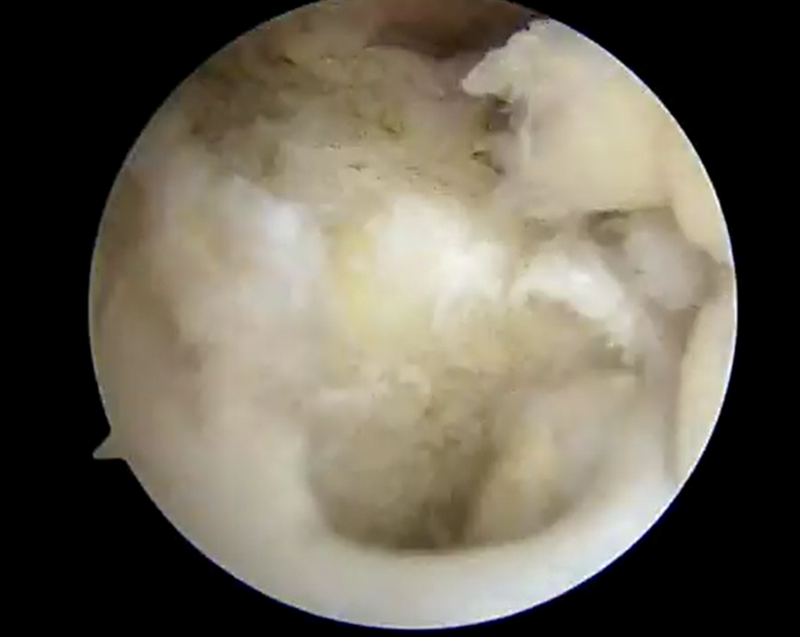

![]() |

| 前十字靭帯損傷部 | 大腿骨側骨孔作成 | 脛骨骨孔作成 |

| 外側半月板問題なし | 内側半月板問題なし | 再建靭帯 |